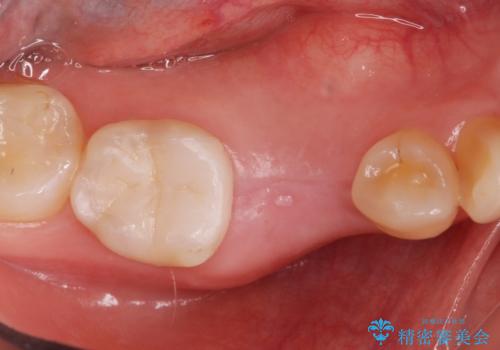

インプラント治療

CTで確認したところ骨の高さや厚みがインプラント埋入できる状態でしたのでインプラント治療を行いました。

- インプラント体、アバット、仮歯、ジルコニアクラウン・42.9万円 e-maxインレー・7.7万円 費用は治療当時の料金となります

適合の良いセラミックが入りました。